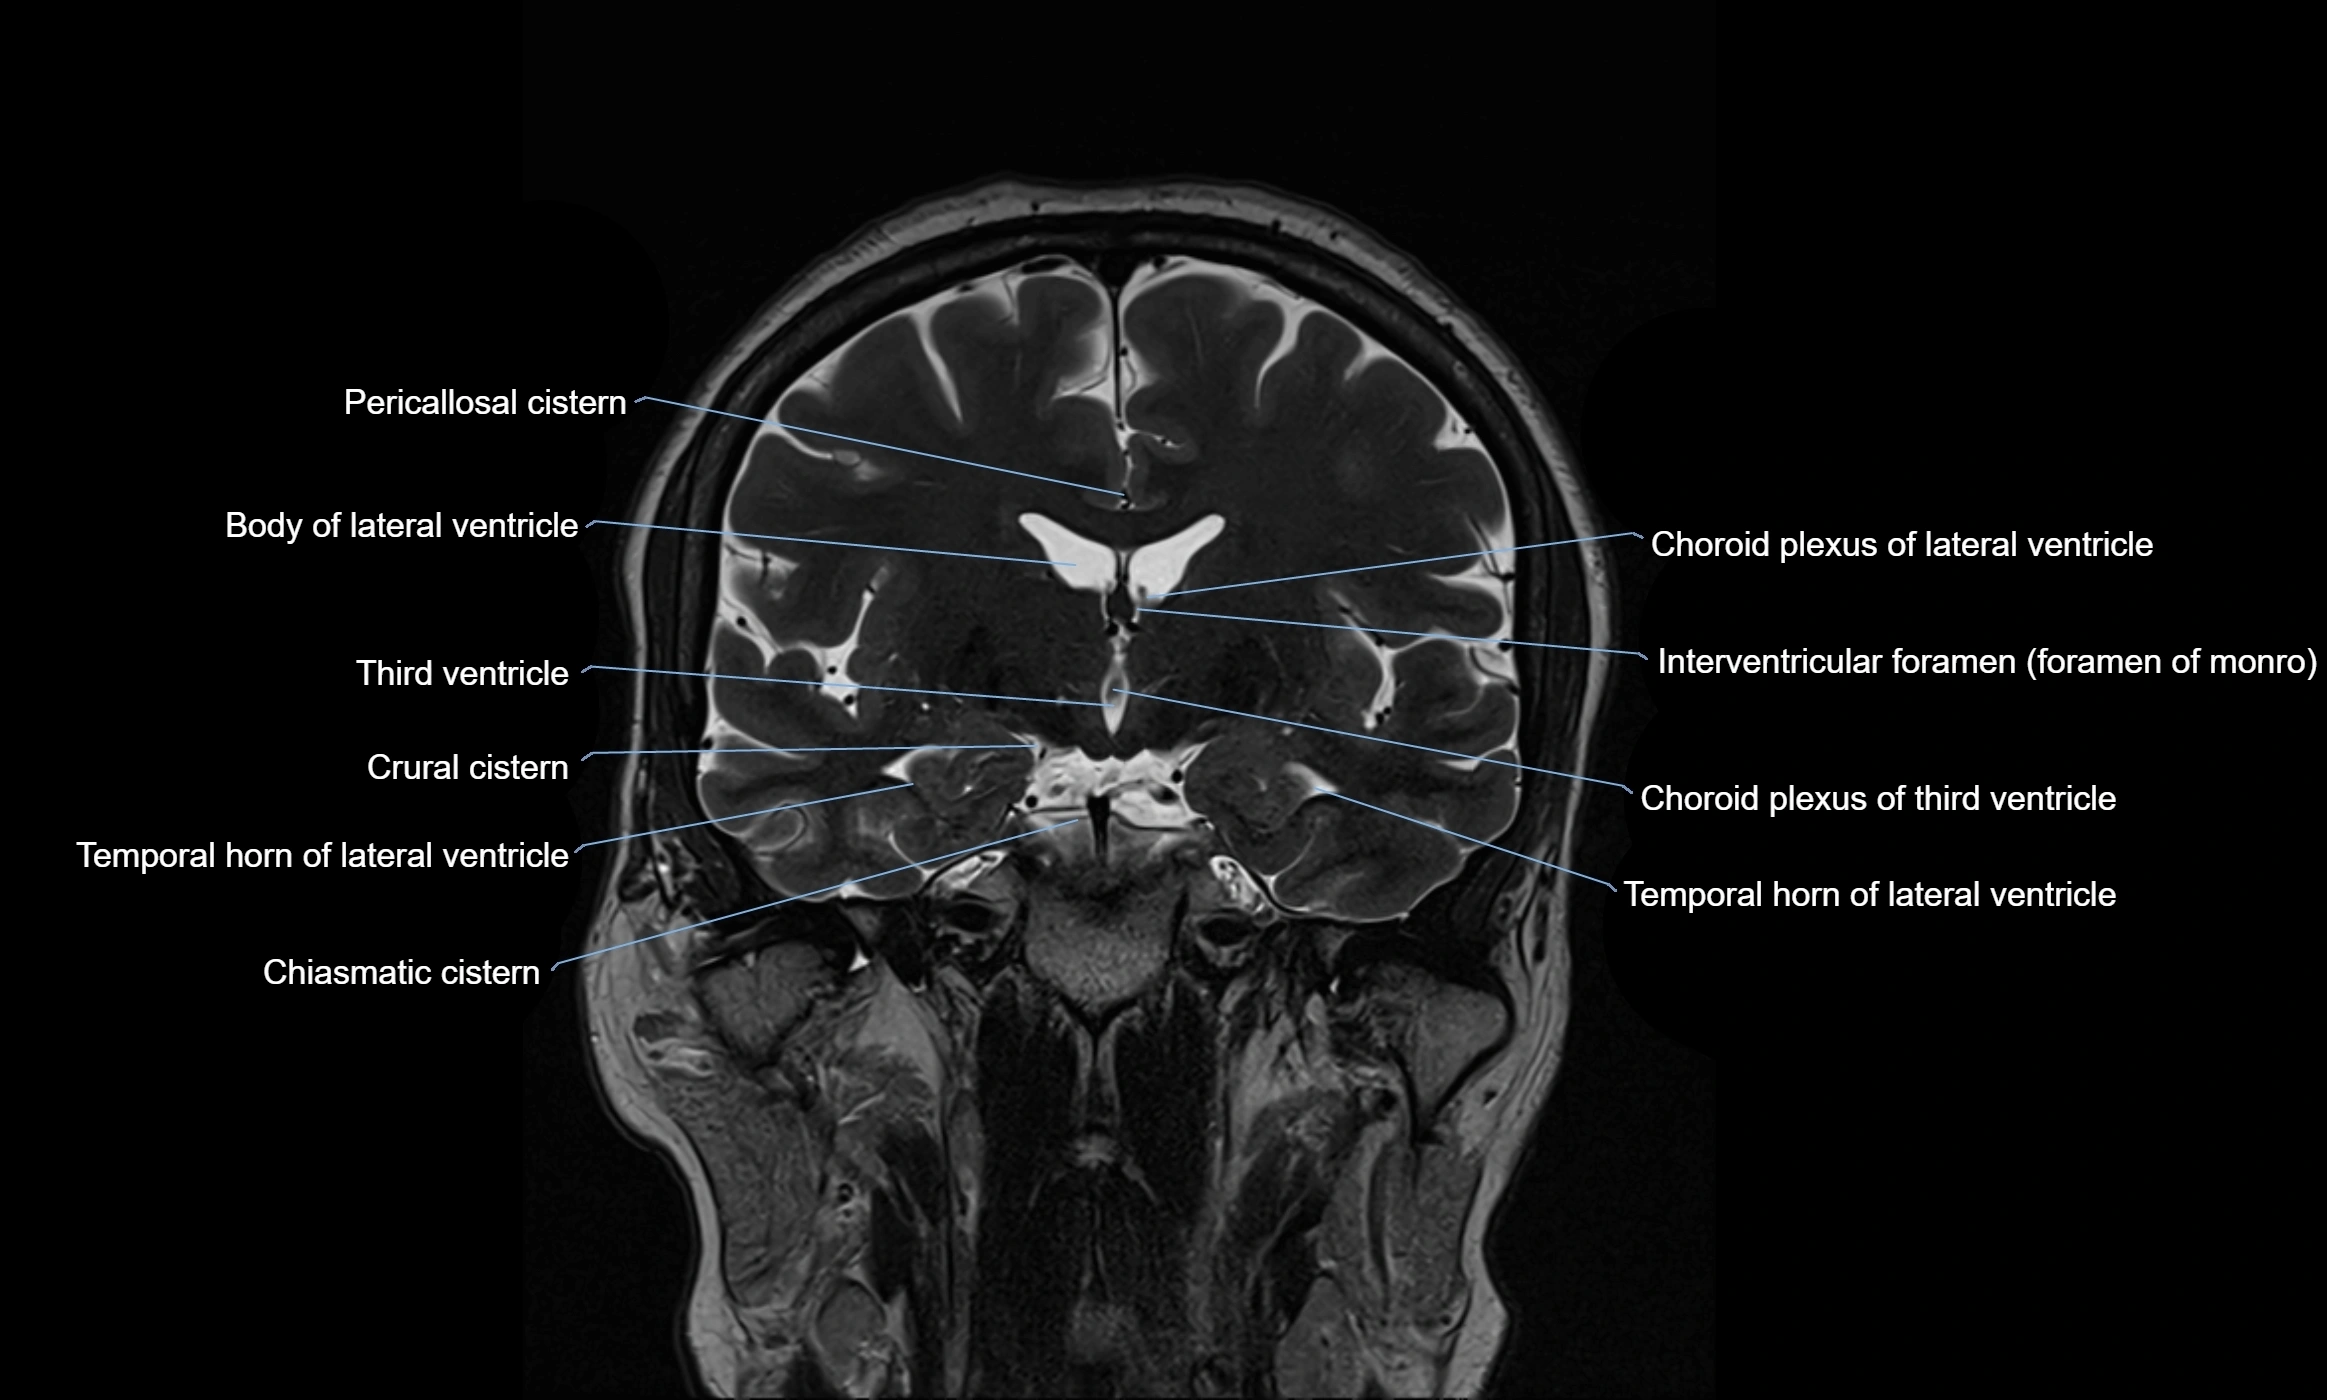

MRI images

image